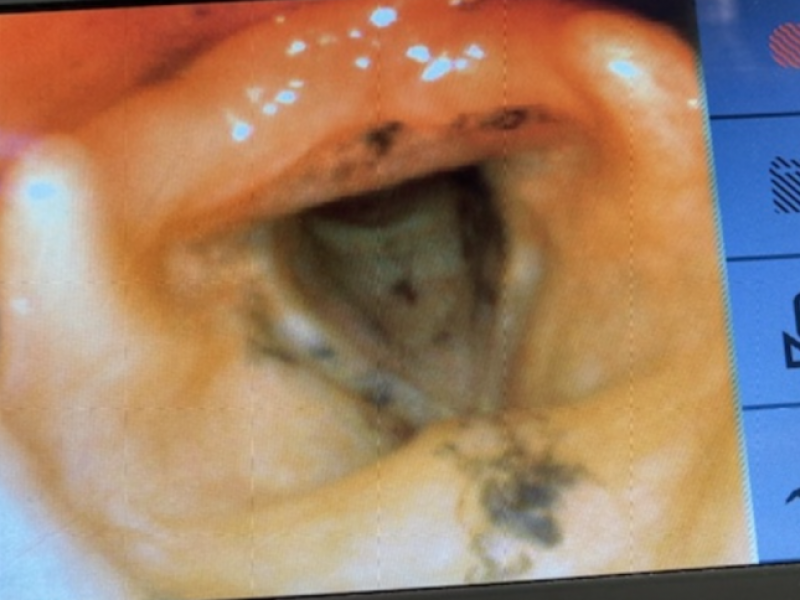

Patient : 30 yo F with PMH generalized anxiety disorder